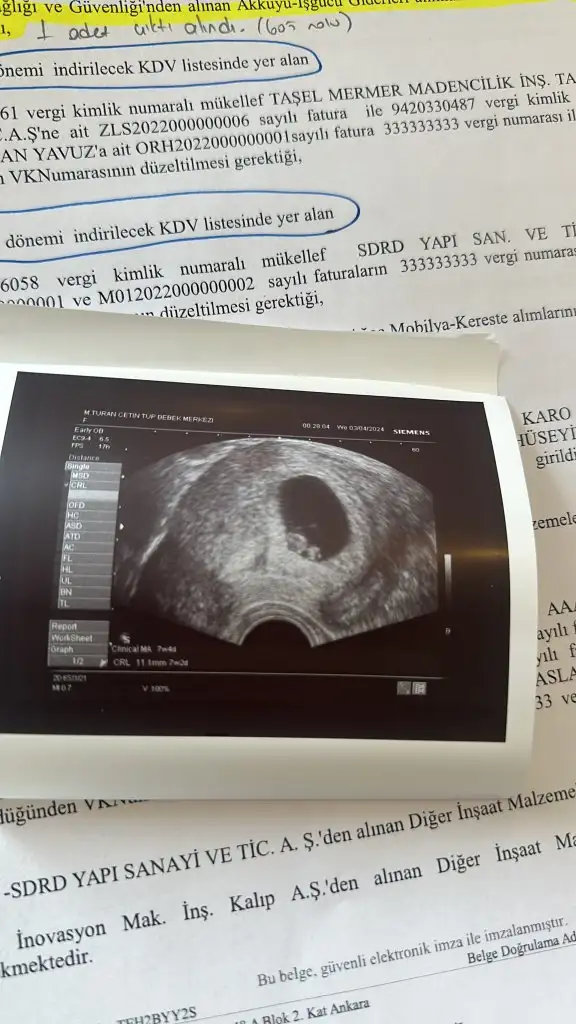

Merhaba 11 haftalik ultrason goruntusu tahmin alabilir miyim :)